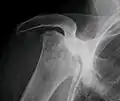

Avascular necrosis most commonly affects the ends of long bones such as the femur (the bone extending from the knee joint to the hip joint). Other common sites include the humerus (the bone of the upper arm),[7][8] knees,[7] shoulders,[8] ankles and the jaw.[7]

In the early stages, bone scintigraphy and MRI are the preferred diagnostic tools.[11]

X-ray images of avascular necrosis in the early stages usually appear normal. In later stages it appears relatively more radio-opaque due to the nearby living bone becoming resorbed secondary to reactive hyperemia.[2] The necrotic bone itself does not show increased radiographic opacity, as dead bone cannot undergo bone resorption which is carried out by living osteoclasts.[2]